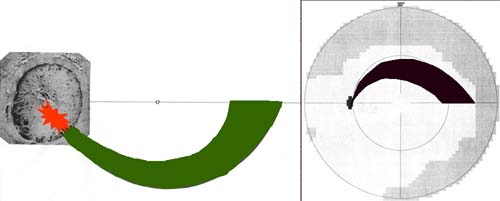

Buňky v centrální části sítnice se začínají diferencovat nejdříve a již za týden jejich výběžky dosahují až k terči. Tak vzniká základ makulopapilárního svazku. Během dalších několika dnů se diferencují gangliové buňky v perifernějších oblastech sítnice. Těm, které rostou z temporální strany, překáží v cestě ke zrakovému nervu již vytvořený makulopapilární svazek a musí jej obloukovitě obejít. Vlákna rostoucí z gangliových buněk z nasální strany takovou překážku na cestě nemají a jejich průběh ke zrakovému je přímý. Tímto způsobem během několika dní vzniká vrstva nervových vláken. Její uspořádání nám umožňuje pochopit lokalizaci skotomů zorného pole.

Výpadky nervových vláken na sítnici a graficky na perimetru podle Minclera

Korelace lokálního výpadku nervových vláken se změnami zorného pole dle Minclera

Když exkavace zasahuje až okraji terče dochází k poškození vláken, která vedou až do temporální části sítnice k tělům gangliových buněk, uloženým v sousedství horizontálního švu. Poškození těchto buněk a jejich axonů se projeví nasálním skokem s arkuátním Bjerumovým skotomem.